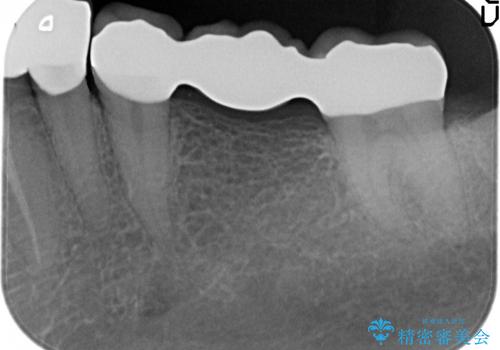

- 笑った時に大きく見えてしまう奥歯の銀歯ブリッジを白くしたいと希望され来院されました。

強度があり、審美性にも優れるジルコニアブリッジに置き替えていく治療計画としました。

- 39.6万円(ジルコニアクラウン×3・仮歯×3)費用は治療当時の料金となります